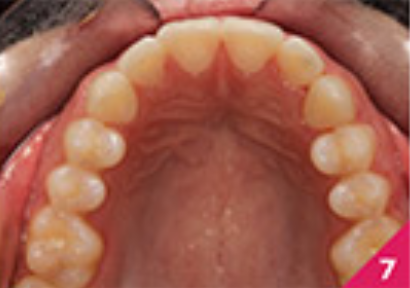

Процес лікування складається із шести фаз, із загальною кількістю 24 елайнери та тривалістю лікування — 16 місяців. Під час лікування, лікар відмітила, що пацієнтка була винятково мотивованою та підтримувала відмінну гігієну ротової порожнини протягом періоду лікування. Для ретенції було застосовано елайнери, ідентичні до тих, які були використані на фінальному етапі лікування 6D елайнерів. На передніх зубах верхньої щелепи були зроблені мінімальні реставрації реконтурування емалі з метою покращення естетичного вигляду.

Лікування показало хороші результати, які можна побачити на фото з 6 по 10. Лікар відмітила, що протягом процесу лікування з'явилася незначна рецесія ясен на правому центральному різці нижньої щелепи. Пацієнтку було скеровано на консультацію до пародонтолога та, можливо, трансплантацію ясен.